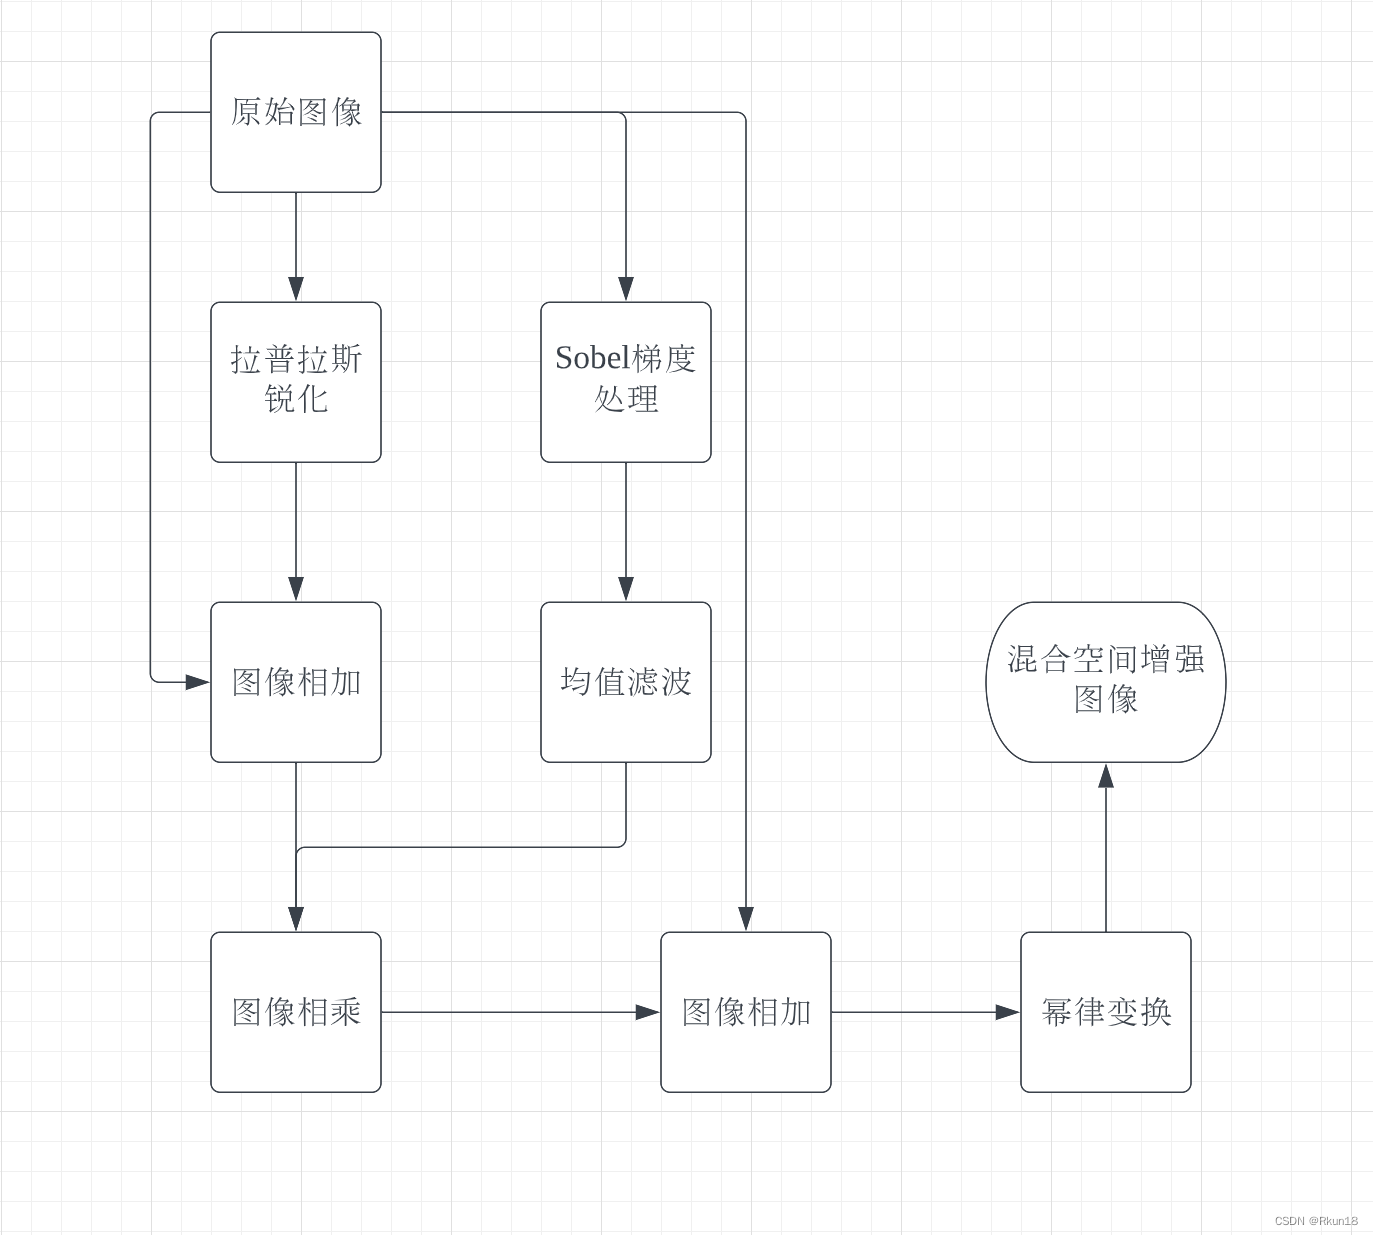

这里使用人体骨骼扫描图像来说明。具体流程如上图,由于人体全身骨骼扫描图像灰度动态范围很窄,并且有很大的噪声内容,使用单一滤波对其增强效果一般。具体作用如图:

从左到右,从上到下依次是:

1:原始图像:

2:1拉普拉斯变化后:

图像全身骨骼扫描,图2为原始图像拉普拉斯变换后的结果,细节信息丰富,同时噪音变多。

3:原始图像与拉普拉斯变换后图像相加得到拉普拉斯锐化增强图像:

4:原始图像Sobel处理 :

图4为原始图像经过Sobel算子处理后结果,边缘信息丰富。

5:均值滤波对4进行平滑:

图4进行空间平滑滤波得到图5,保留图像边缘信息,同时减小了噪声。

6:3*5得到的掩蔽图像:

将图3与图5相加得到图6,发现图6的强边缘优势和可见噪声相对减少。

7:原图与掩蔽图像相加得到的锐化增强图像:

图像的大部分细节更清晰。

8:对7进行灰度幂律变换得到最终结果:

图8进行幂律变换后增大了一些噪声,但同时人体结构更加清晰完整,人体轮廓清晰度也有一定提高。

上图更能直观地观察到图像变换后的差异。

文章介绍了混合图像增强技术在处理人体骨骼扫描图像中的应用,包括使用拉普拉斯变换增强细节,Sobel算子突出边缘,以及灰度幂律变换优化图像对比度。通过一系列图像处理步骤,实现了在保持细节的同时减少噪声并增强图像清晰度。